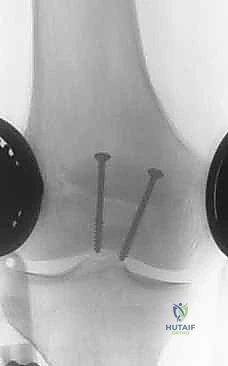

We will use two 1.6 to 2.0 mm Kirschner wires to span the fracture in parallel.

4. Second K-wire: Repeat this process for the second K-wire, ensuring it is parallel to the first and spaced appropriately to provide a stable construct.

* Here, both K-wires are in place, providing initial stability.

5. Depth Control: Ideally, the Kirschner wires should be positioned approximately 5 mm below the anterior surface of the patella. This ensures they are subcortical but not so superficial as to risk skin irritation.

> SURGICAL WARNING: Avoid penetrating the articular surface with your K-wires. Use fluoroscopy to confirm appropriate placement and depth. A lateral fluoroscopic view is invaluable here.